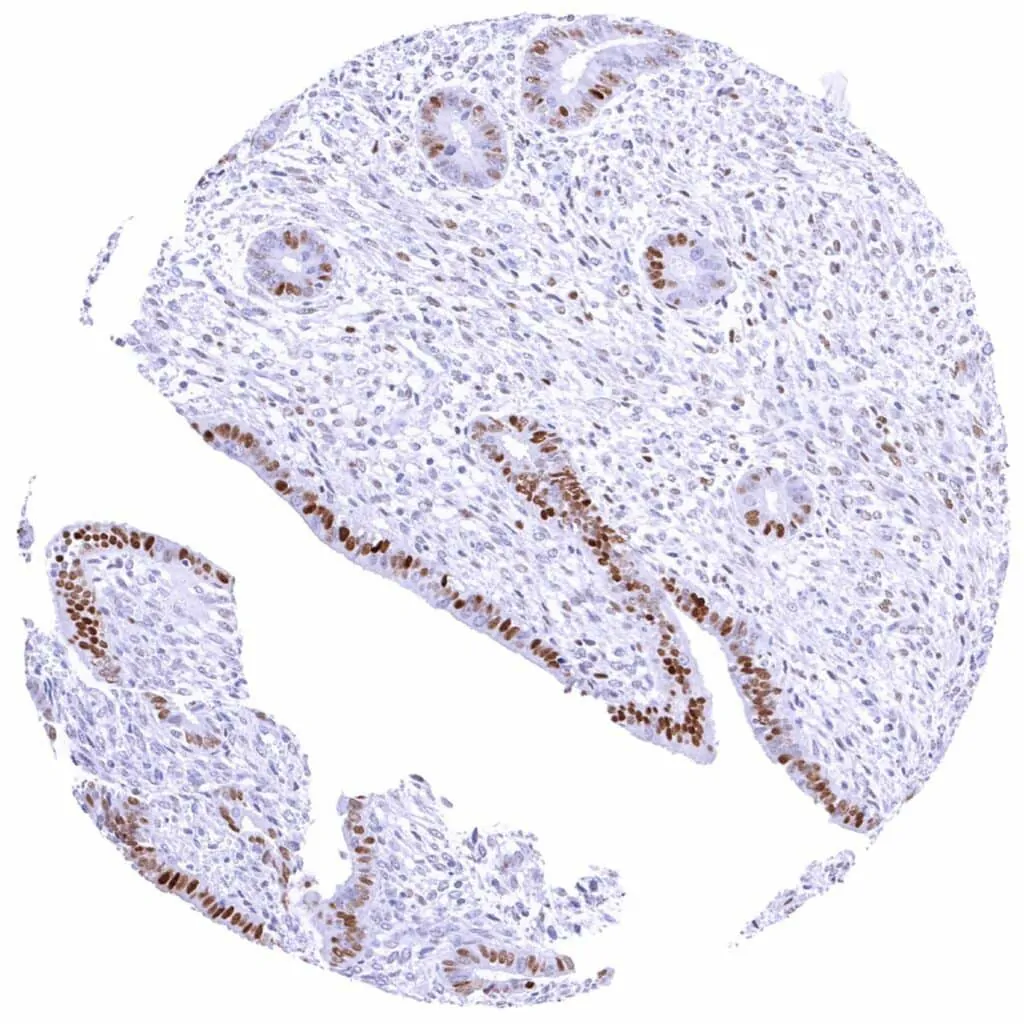

Rectum, mucosa – Weak to moderate Cyclin E1 staining of a large subset of crypt cells